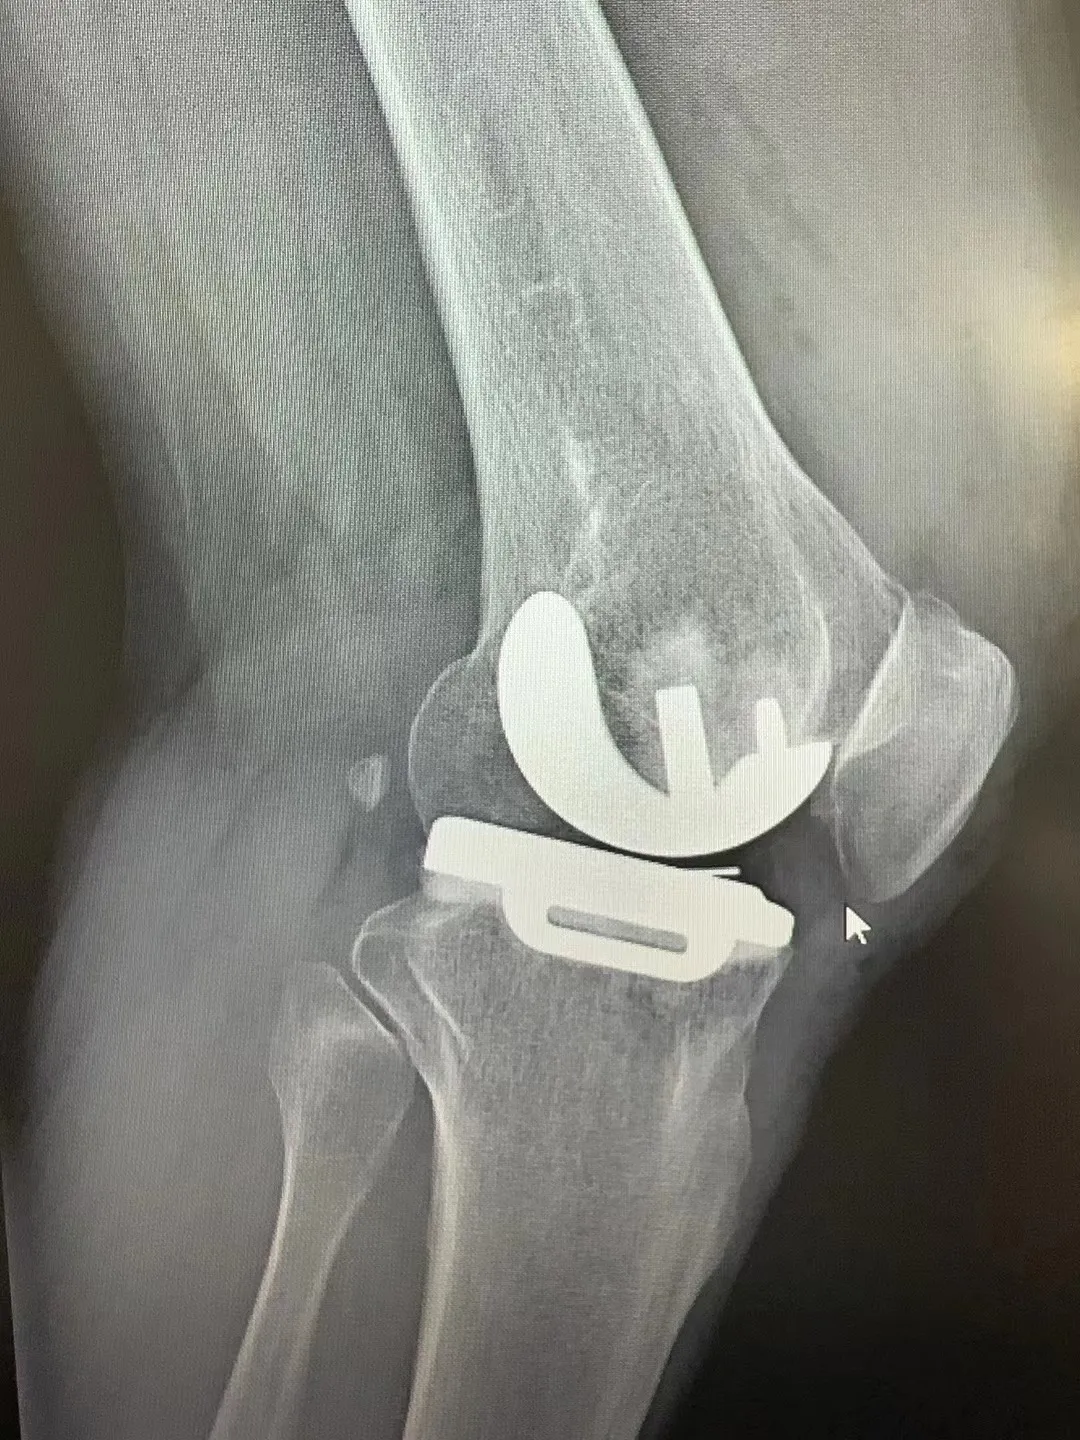

术后患者膝关节情况